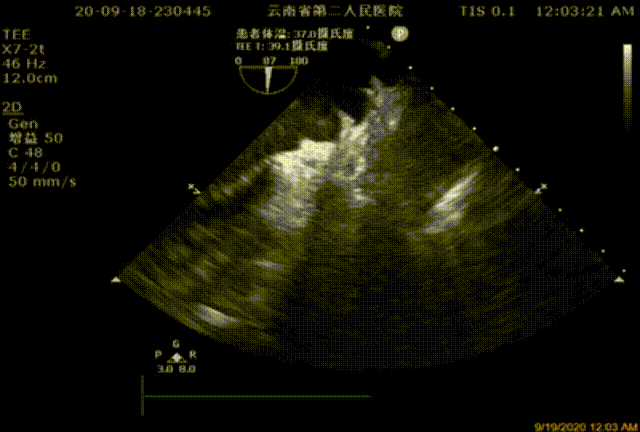

患者阵发性心房扑动2年余,已行射频消融术,术后随访为短阵房速,3月前行食管超声左心耳内见血栓;欲求行左心耳封堵术入院,规范抗凝治疗后次入院后再次复查食道超声未见血栓。血栓栓塞/出血危险评分:CHA2DS2-VASc=3分,HAS-BLED=4分。

图2:2020年9月TEE检测未见心耳血栓

同时经食道超声监测心脏、心包及检测左心耳结构(18/28,17/28,18/29,22/28),未见心房及心耳血栓。